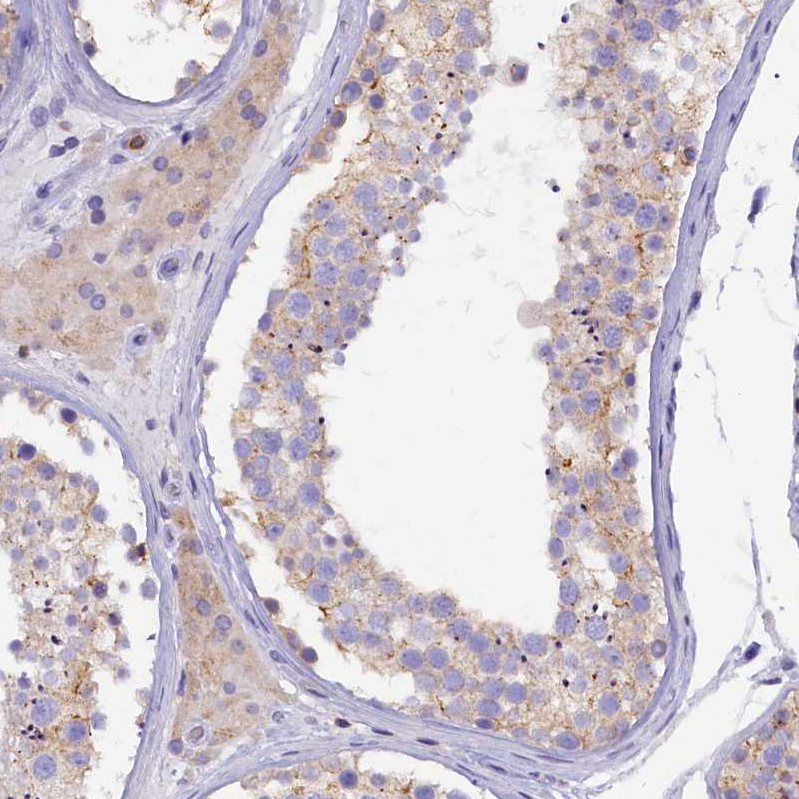

Immunohistochemical staining of human testis shows moderate cytoplasmic positivity in cells in seminiferous ducts and Leydig cells.